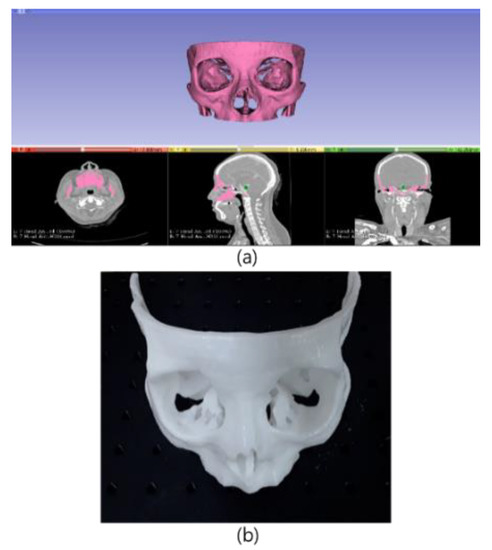

4.2. Design of the Phantom